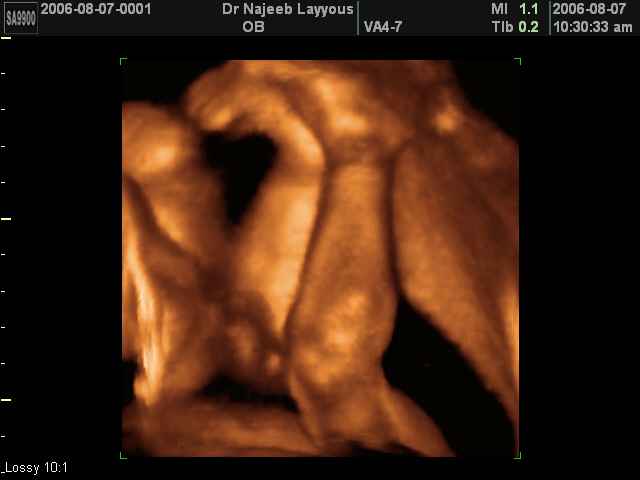

3D Ultrasound Scan Photos of Fetal Limbs | Dr N Layyous

3D Fetal Limbs Ultrasound Scan Photos